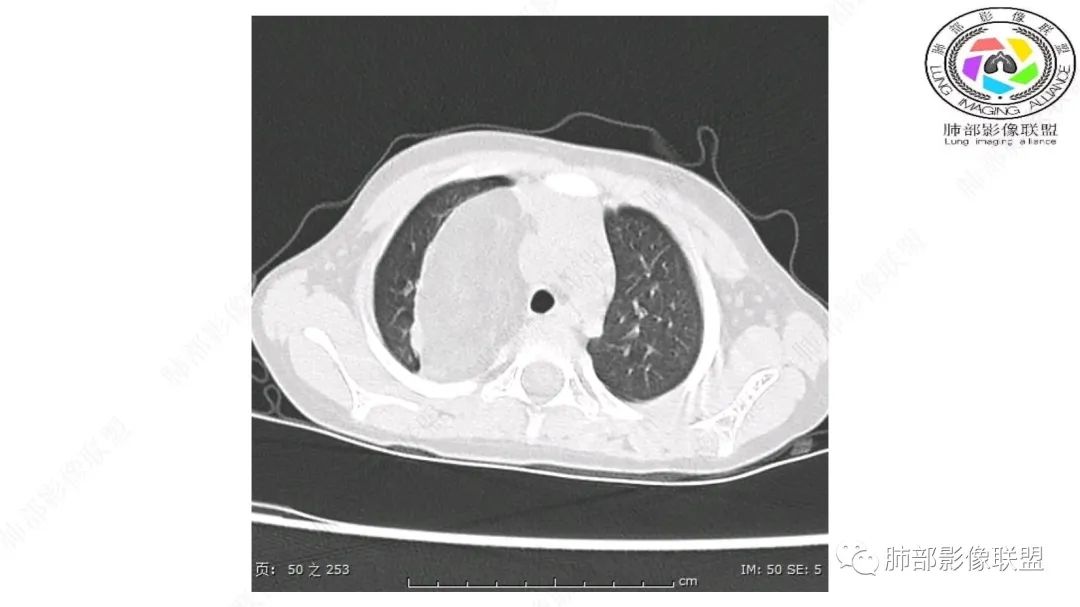

患儿3岁 咳嗽检查发现纵隔占位。右肺上叶受压表现,占位以脂肪组织密度为主,似见分隔,首先考虑为脂肪母细胞瘤,鉴别脂肪瘤,畸胎瘤。

跨肺门,包绕肺血管分支,邻近肺组织受压肺不张。

病灶属于交界区,主体位于肺内,占位效应明显,前方突入胸壁,胸腺受压变形,胸膜显示欠清楚;病灶包绕上叶肺动脉;似乎有体动脉供血。符合肺内的点:包绕上叶肺动脉分支;符合纵隔的点:前方似乎突入胸壁,与胸腺关系比较密切,但是与上腔静脉的关系提示病灶不支持纵隔来源,前纵隔的常规会将上腔静脉受压后移、外移,这是不符合的。

手术记录:见右肺上叶肿物,肿物与右肺上叶关系密切。与纵隔无粘连,逐步分离肿物,见肿物大小约6cm*5cm,边界清楚,于右肺上叶粘连,边界清楚,肿物包绕右肺上叶血管及支气管。超声刀逐步游离肿物,完整切除肿物,右肺上叶肺组织无破溃,表面无出血。

2.肺动脉穿行也许是肺内来源最重要支持点!

CT扫描对脂肪类肿瘤常有独到价值。肿块孤立、边界清楚,未见周围浸润,较均匀脂肪样低密度,高度提示为良性!